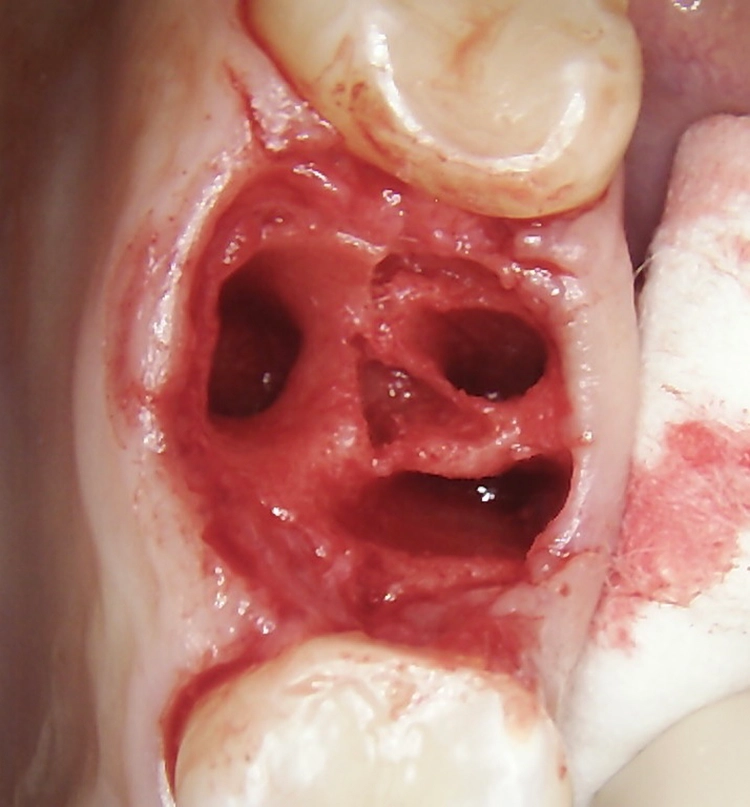

Bei dem balkonförmigen Implantat blieben die Alveolarkämme und der Kronenansatz erhalten (Abb. 4c und d). Der Spalt zwischen dem Implantat und der bukkalen Lamelle wurde mit A-PRF und einem Kollagenblock aufgefüllt, so dass keine zusätzliche Knochenaugmentation erforderlich war. Zusätzlich wurden PRF-Matrizen um, über, unter und neben dem Implantat im Knochen-Implantat-Raum positioniert (Abb. 1 bis 4b). Außerdem kam eine optionale Einheilscheibe (6 x 8 mm) zum Einsatz, um das Kollagen und die PRF zu sichern (Abb. 3b). Die Implantate zeigten bei einem Drehmoment von 35 Ncm Stabilität, welche mit dem Periotest-Gerät von Medizintechnik Gulden getestet wurde. Die Werte des Implantatstabilitätstests, die im Bereich von –8 bis 0 lagen, wurden als ideal für die Belastung angesehen (Tab. 3).

Abb. 2: Repräsentativer Fall von ABH Grad B Septus Typ II. a) Ansichten vor der Installation. Röntgenaufnahme der periapikalen Läsion an einem wurzelkanalbehandelten Molaren und klinische Ansicht der Typ-II-Socket nach der Extraktion. b) Die Ansichten nach der Installation zeigen das Implantat innerhalb des interradikulären Septums und das über dem Implantat platzierte A-PRF. c) Nachuntersuchungen nach 10 Tagen bzw. 2,1 Monaten. Die Röntgenaufnahme zeigt die Knochenbildung zwischen der Sinusmembran und dem apikalen Teil des Implantats. d) Jüngste Nachuntersuchung nach Einsetzen der Prothese.

Abb. 3: Repräsentativer Fall von Grad A Typ I. a) Präoperative Ansicht. Röntgenbild der periapikalen Läsion an einem wurzelkanalbehandelten Molaren. Die Höhe des Alveolarknochens zeigt Grad A an. b) Klinische und radiographische Ansicht der Implantatinsertion unter Verwendung einer Einheilscheibe mit großem Durchmesser (6×8 mm). A-PRF wurde um das Implantat und unter der Scheibe platziert. c) Nachuntersuchung nach 5,9 Monaten vor und nach der Zementierung und Aufbereitung. d) Jüngste Nachuntersuchung nach Einsetzen der Prothese

Abb. 4: Repräsentativer Fall von Grad A Typ III. a) Ansichten vor der Implantation. Röntgenbild der periapikalen Läsion an einem wurzelkanalbehandelten Molaren. b) Die Extraktionsalveole zeigt ein interradikuläres Septum vom Typ III (B).